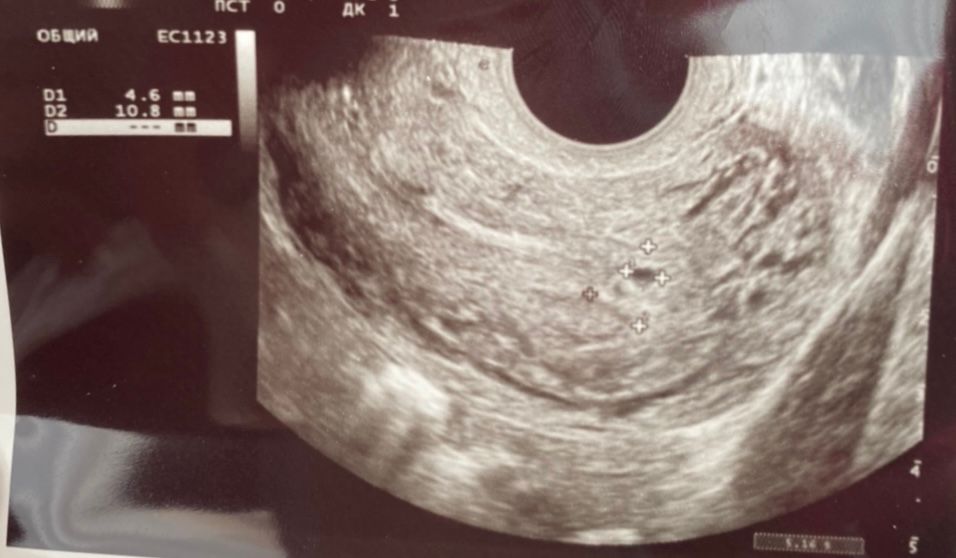

Измерение роста цикла и овуляция: результаты гемотеста и узи